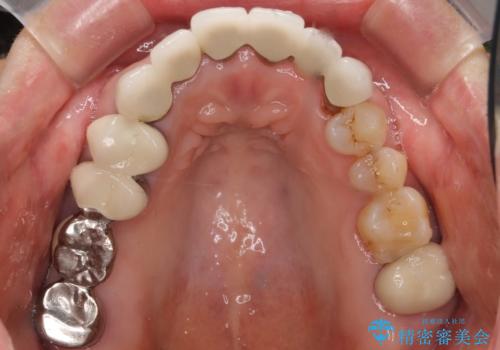

また、古い被せ物はブリッジではない右上321も連結されていましたが、1本1本の歯の動揺がなく連結する必要がないと判断し単冠による補綴を行いました。

単冠の部位は天然歯のようにフロスを通すことができるため、セルフメンテナンスもしやすくなったと患者様に喜んで頂けました。